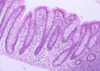

Which of the following statements concerning the image above is FALSE?

- All of the cells in this epithelium are in contact with the basement membrane

- The epithelium contains some cells which secrete mucus

- This epithelium is ciliated

- This is a pseudostratified columnar epithelium

- This is a stratified columnar epithelium

- This is a stratified columnar epithelium.

This is pseudo-stratified columnar ciliated epithelium from the trachea. All of the epithelial cells are anchored to the basement membrane. The cells with pale cytoplasm are goblet cells that secrete mucus.